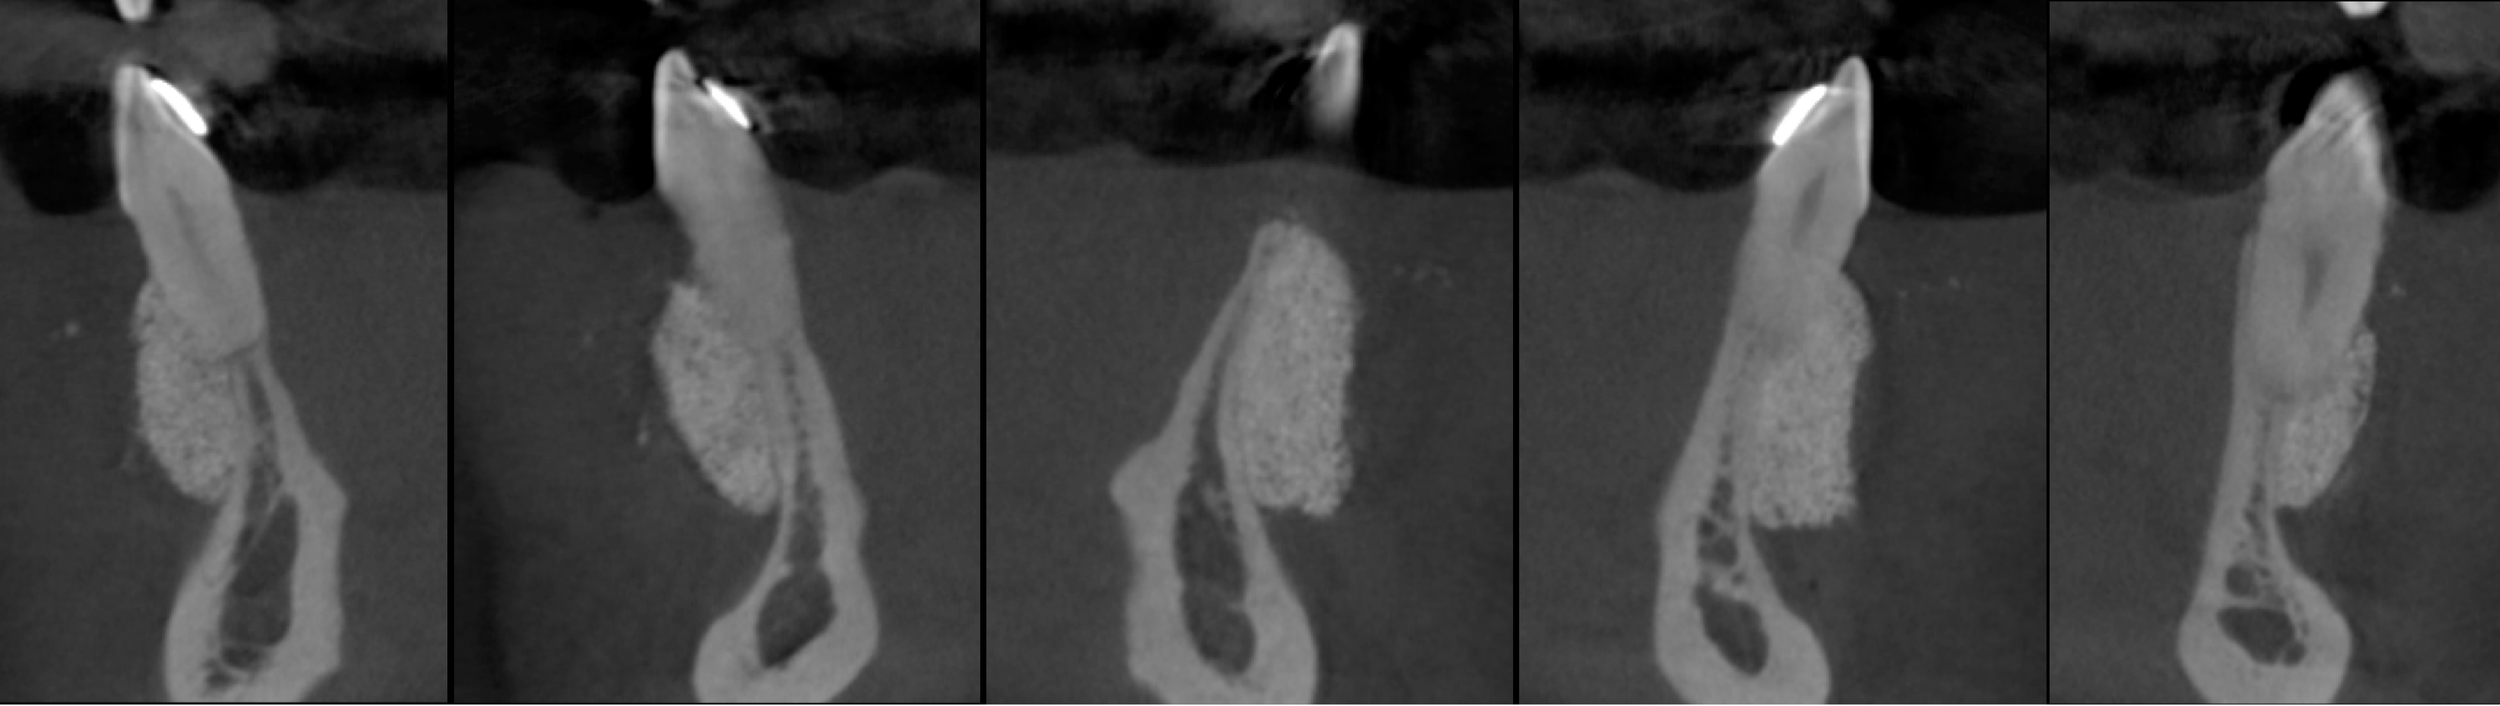

CASE 7. KNIFE-EDGE RIDGE